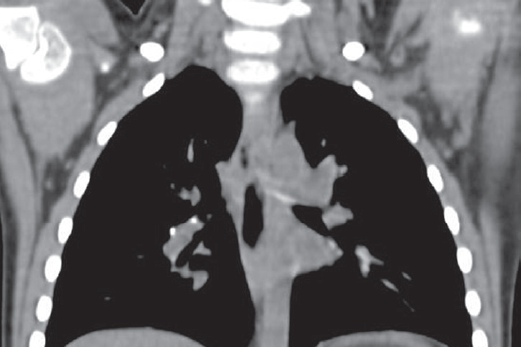

The problem of young children tuberculosis in Russian Federation (RF) still remains actual because of high-level spread of disease between adults and anatomical and physiological features of this period of childhood. The young children morbidity in Saint Petersburg, 2015-2017 became 7.1-5.3 of 100,000 population. It is typical for the age group from 0 to 3 years that tuberculosis development often becomes into the state of active disease and does not stop as latent infection. Our research includes children of early age whose tuberculosis has been diagnosed in 2012-2017 – totally 101 children. One third of the patients were not vaccinated with the BCG vaccine, moreover 41.9% were not vaccinated because of perinatal contact with HIV and 22.5% because of perinatal contact with HIV + hepatitis C. Each second child related to social risk group. Contact with MBT expectorator has been found for 64% of children: drug resistance for at least one drug has been met in 70% cases, including 19% MDR-TB and 11% XDR-TB. Immunology diagnosis analysis showed up that at the moment of the disease detection the tuberculin skin test in 93% cases was positive, but often moderately expressed, meanwhile the Diaskintest was positive in 92% cases, mainly hyperergic or expressed. Objective diagnosis for 79% patients showed symptoms of intoxication of different degrees, for 50% – micropolyadenia, local symptoms – only for 13%. Structure of diagnosis contained mainly intrathoracic lymph nodes tuberculosis (67%), gene ralized forms – 9%, extrapulmonary – 1%. Complicated tuberculosis has been observed in 38% cases. After treatment recovery has been achieved for 98 children, but also 3 lethal cases occurred – all for non-vaccinated infants in case of severe concomitant disease. Conclusion: nowadays development of active tuberculosis in young children is caused by increasing quantity of BCG-unvaccinated newborns – mostly because of perinatal HIV-contact, and poor social conditions.